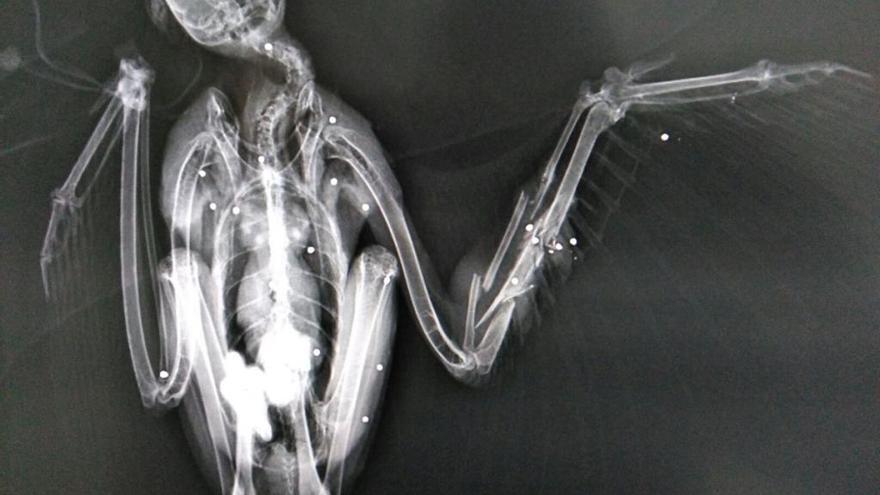

La Secretaria de Medi Ambient i Sostenibilitat de la Generalitat ha informat de l'ingrés al Centre de Fauna dels Aiguamolls de l'Empordà d'un aligot ferit com a conseqüència d'haver estat víctima d'uns trets. Aquesta au procedent de Castell d'Aro presenta 22 perdigons al seu cos.

L'aligot, que ha estat rescat per agents rurals, és una espècie protegida. El Centre de Fauna farà tot el possible per salvar-li la vida.